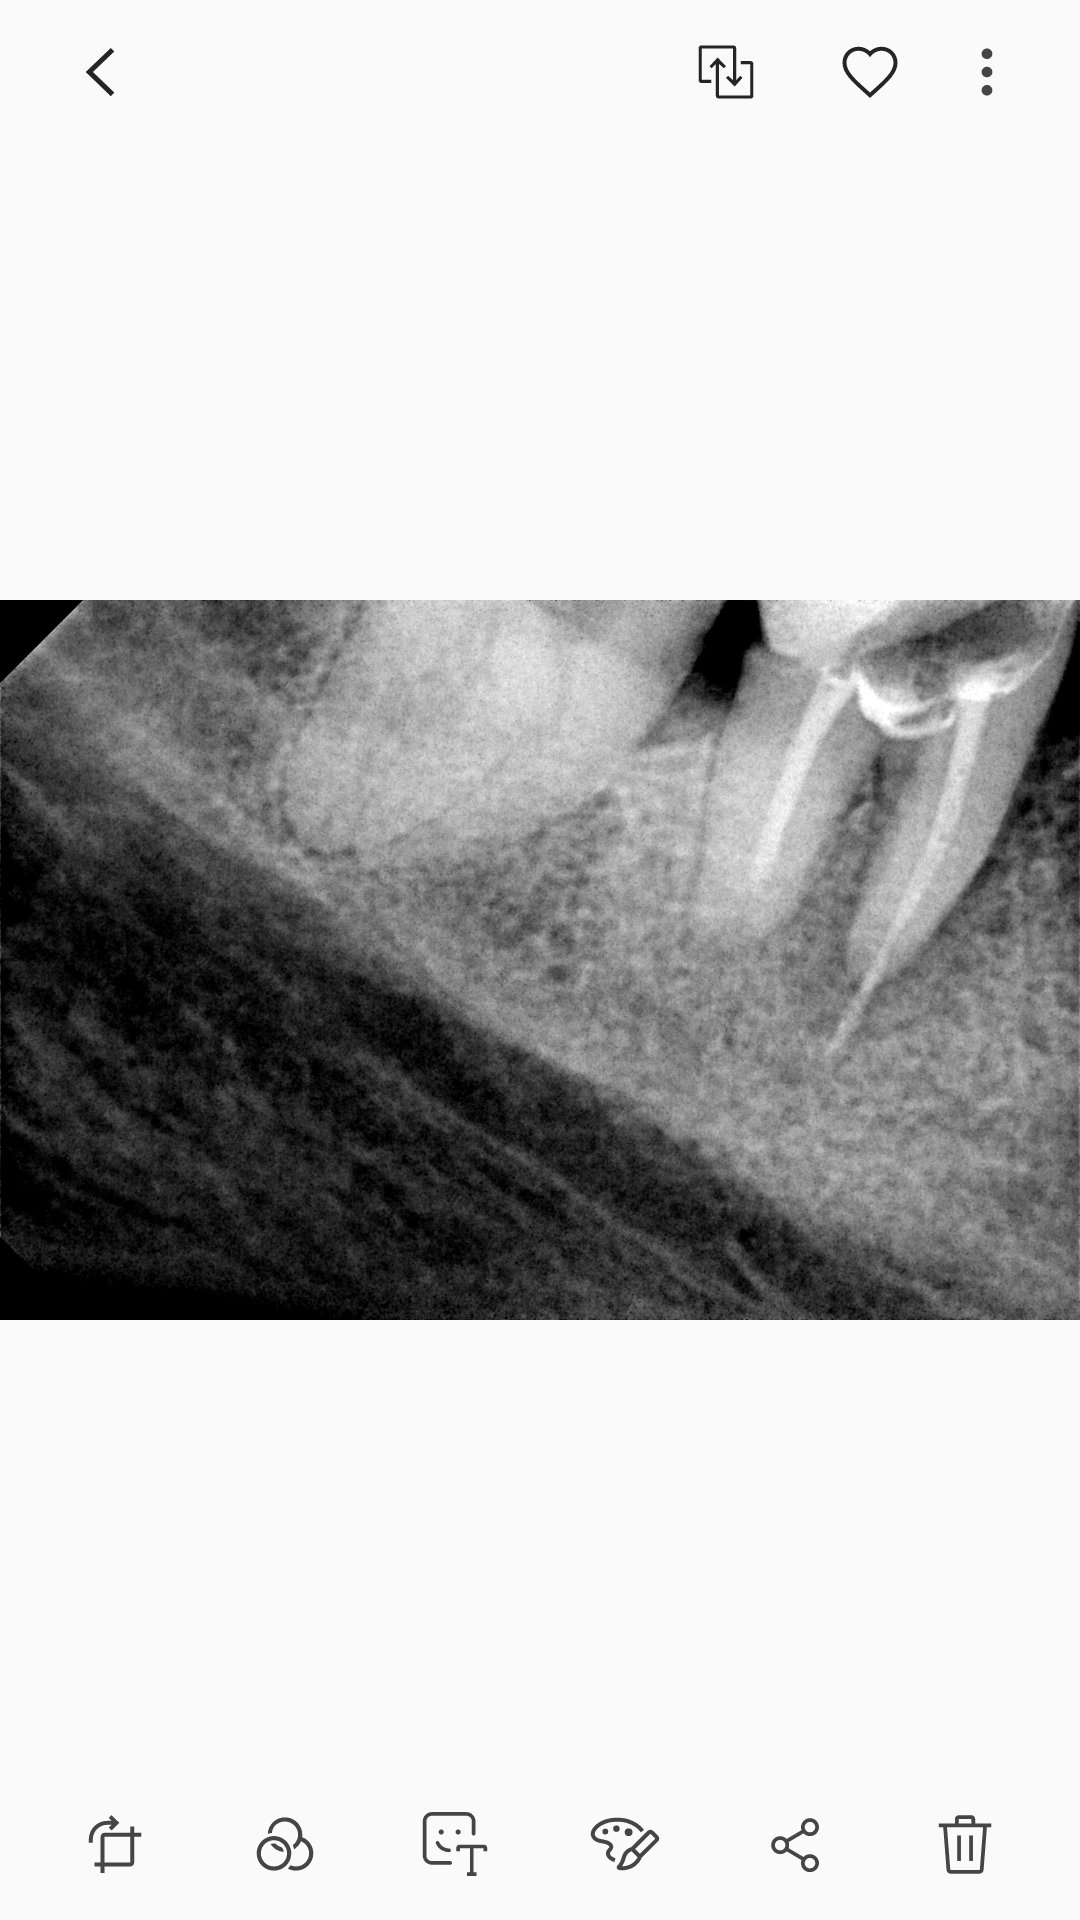

След като в четвъртък ми поставиха щифта и пломбираха зъба, от вчера има вече болка. Пия парацетамол, т.к. док каза че ще има неразположение заради препълването на канала и да си вземам по един. Но вече си е болка, нощес се събудих с топтене на зъба. Днес след парацетамол сутринта и два ибупрофена на обед, болката и туптенето в зъба отново са на лице. Искам да направя и едно уточнение много важно според мен: когато ми лекува корените, док не можа да влезе в единия и двата пъти и го остави така; каза, че проблема бил в другия корен. Според Вас тази болка нормална ли е в резултат на изтичането на пълнежа от корена или трябва да посетя стоматолога ОТНОВО???

Принципно се прави секторна снимка след запълването, за да се проследи добре и докрай ли е запълнен канала. Принципно има възможност да е възникнала инфекция в зъба поради недобро запълване, но тук само гадаем.